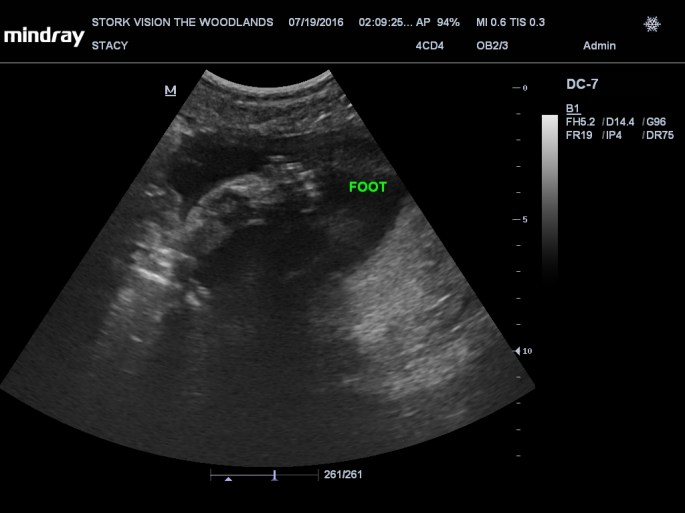

Best moment the week: Seeing Juliette on the 3D/4D ultrasound. So amazing!

Symptoms: Super moody, no patience, acne is coming back, restless, feet have a little bit of swelling, tired all the time and feeling like I’m having a hard time breathing. Juliette started to hiccup (or at least I started to feel it) this week! She usually does it every night when I first lay down to sleep. I have horrible pregnancy insomnia. I’m also peeing a lot too in the middle of the night again.